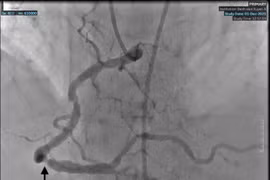

Khoảng 20% trẻ nhỏ nhập viện vì suy tim là do hẹp eo động mạch chủ. Nếu không được chữa trị kịp thời, hẹp eo động mạch chủ sẽ dẫn đến thiếu máu, tăng huyết áp, phình và vỡ mạch não, suy tim, tăng áp lực động mạch phổi…